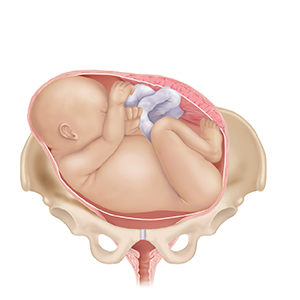

A baby (the fetus) often moves down between the pelvic bones (descend) before birth. If this is your first pregnancy, this may happen 2 to 4 weeks before labor. With repeat pregnancies, the baby may not “drop” until labor begins. The baby usually moves down headfirst. If your baby is not in a safe position for birth, or if there is a problem with the placenta, you may need special care. A cesarean section delivery may be needed.

Placental abruption.Placenta separates from the uterus.

Placenta previa.Placenta blocks the cervix.